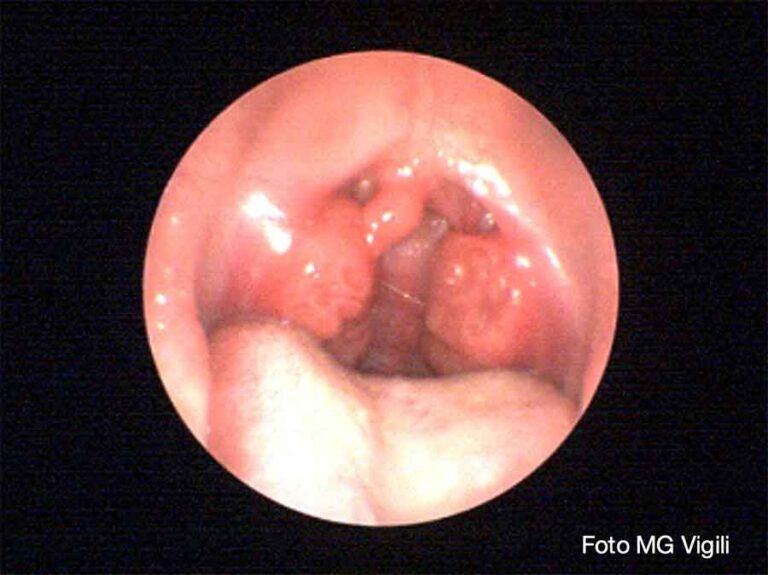

Importanza della pH-impedenzometria nella determinazione del Reflusso Faringolaringeo nei pazienti con granuloma laringeo da contatto